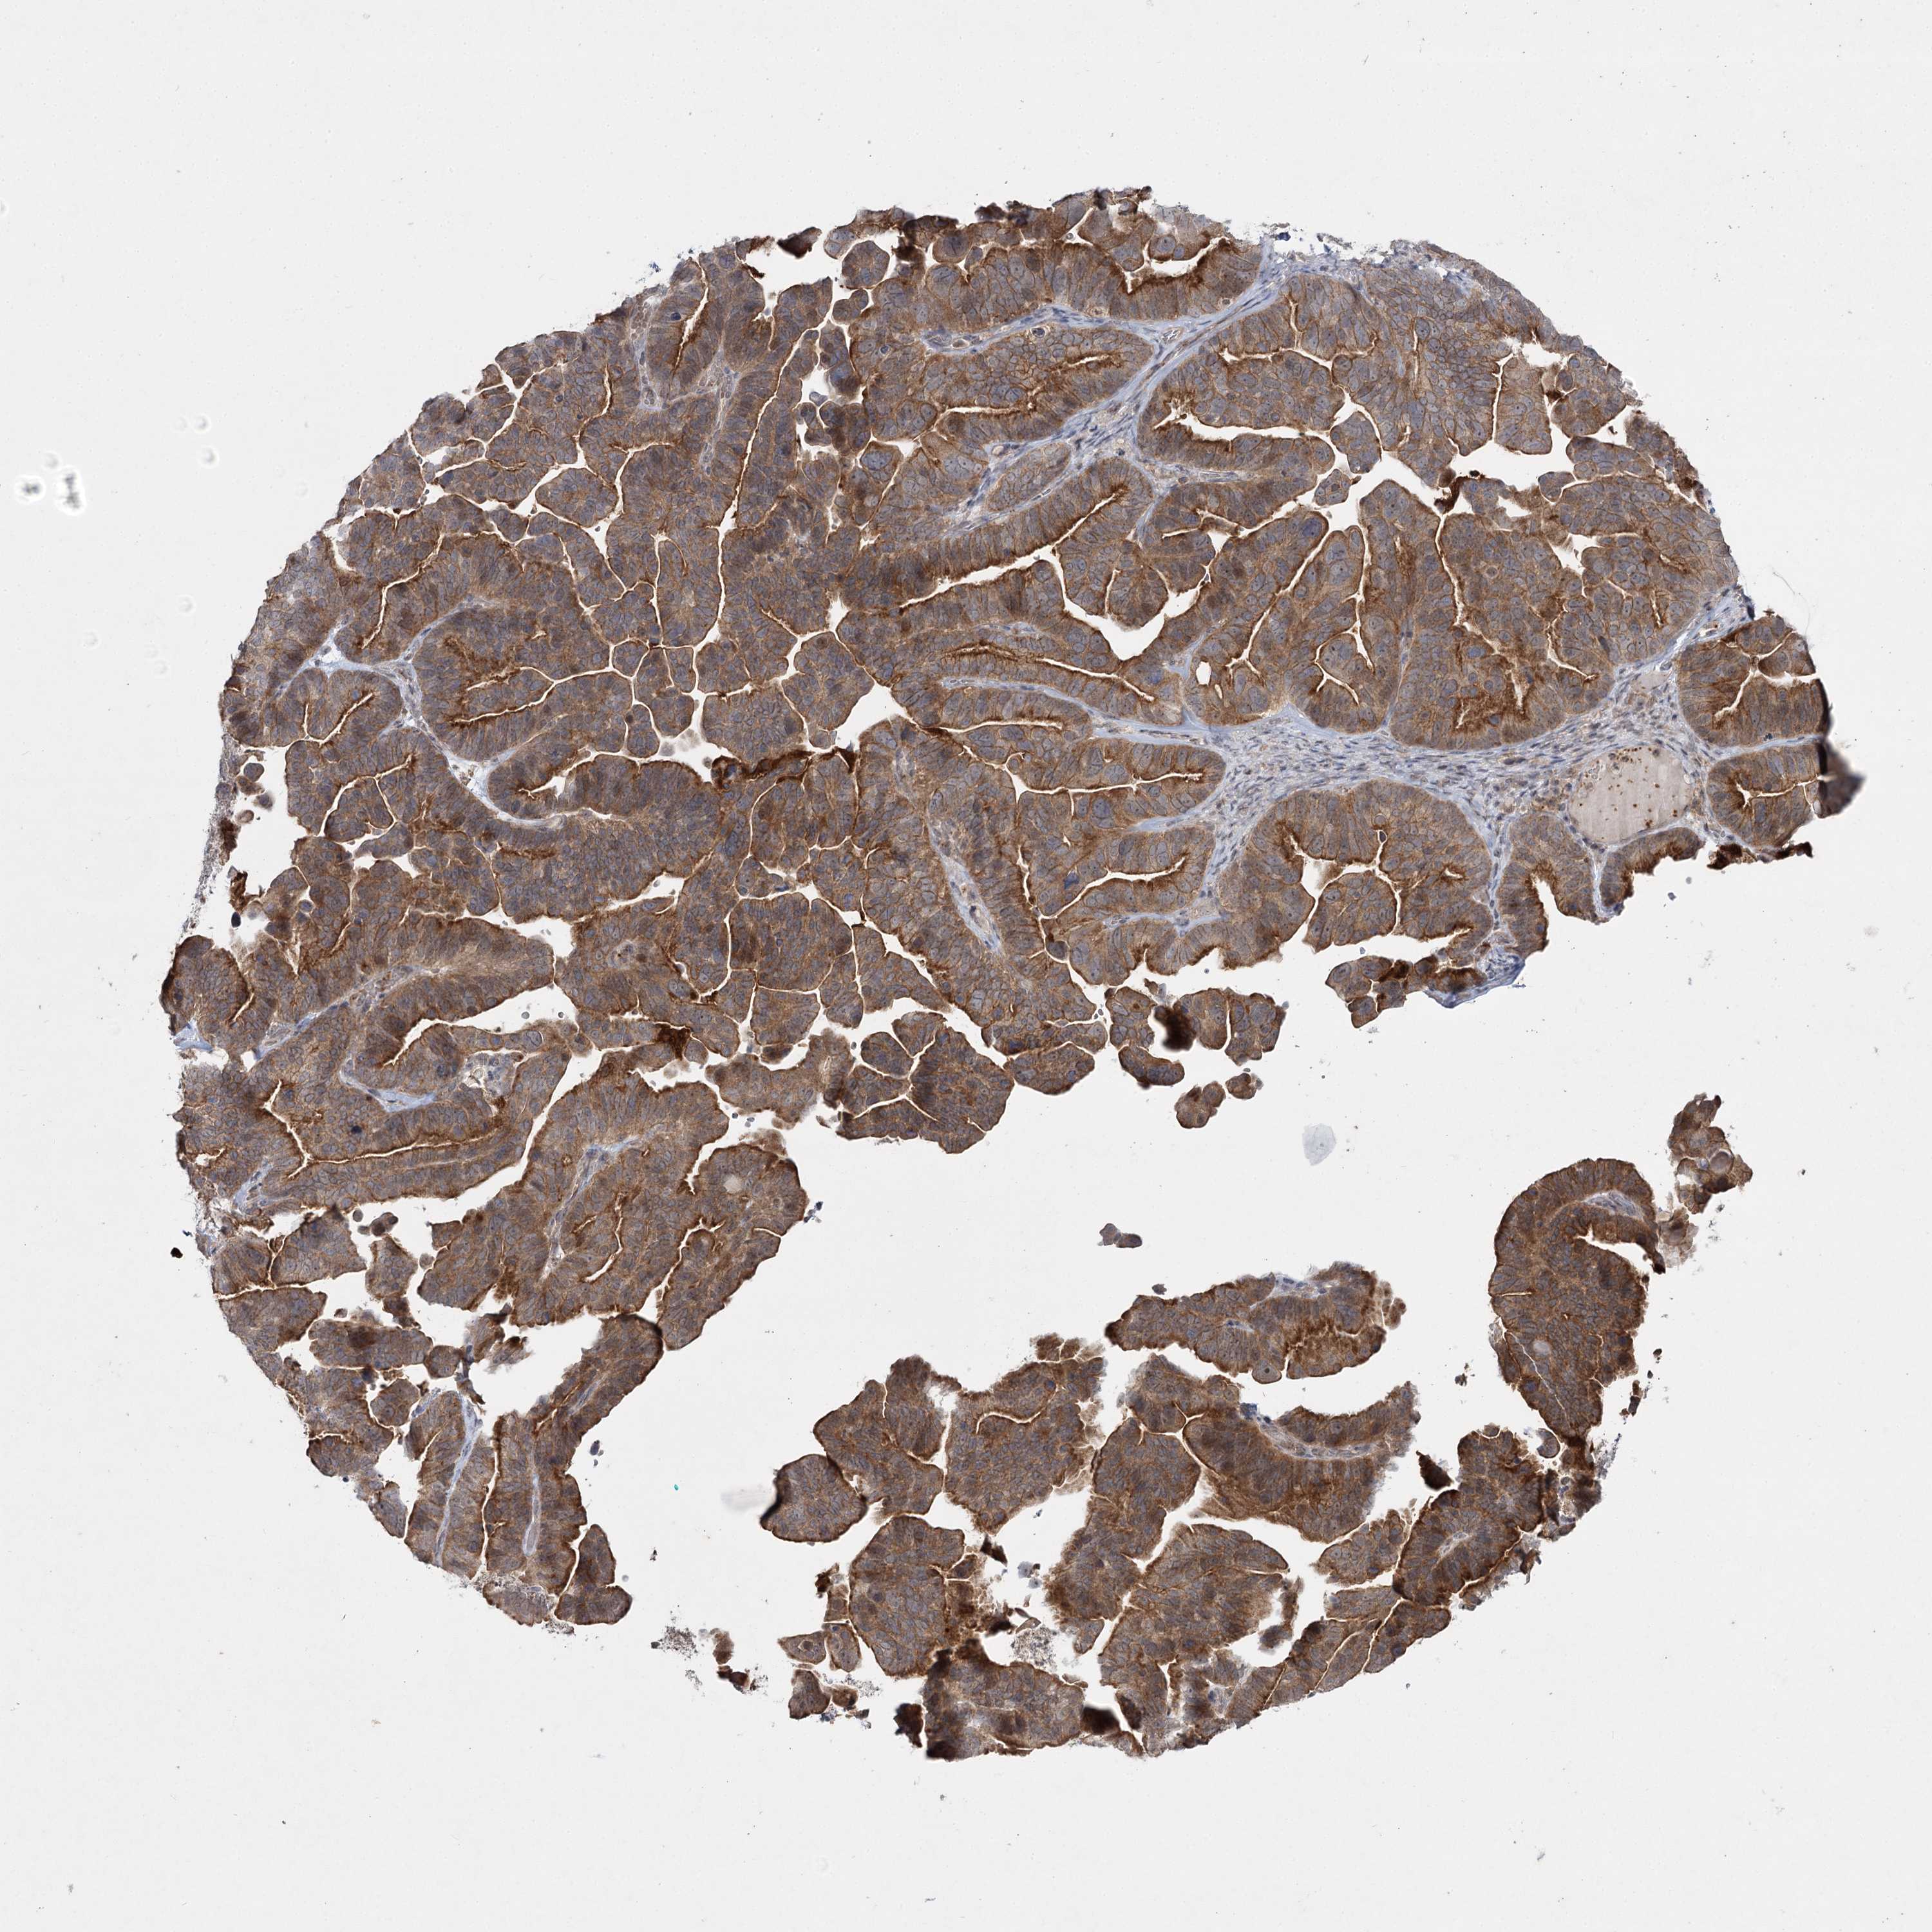

OVARIAN CANCER - Protein expressioni

A mouse-over function shows sample information and annotation data. Click on an image to view it in a full screen mode. Samples can be filtered based on level of antibody staining by selecting one or several of the following categories: high, medium, low and not detected. The assay and annotation is described here.

Note that samples used for immunohistochemistry by the Human Protein Atlas do not correspond to samples in the TCGA dataset.

Antibody stainingi

Antibody staining in the annotated cell types in the current human tissue is reported as not detected, low, medium, or high, based on conventional immunohistochemistry profiling in selected tissues. This score is based on the combination of the staining intensity and fraction of stained cells.

Each image is clickable and will lead to virtual microscopy that enables deeper exploration of all samples and also displays staining intensity scores, fraction scores and subcellular localization as well as patient and tissue information for each sample.

Antibody HPA038084

Staining

High

Medium

Low

Not detected

Intensity

Strong

Moderate

Weak

Negative

Quantity

>75%

75%-25%

<25%

None

Location

Nuclear

Cytoplasmic/membranous

Cytoplasmic/membranous,nuclear

Cystadenocarcinoma, serous, NOS

Carcinoma, endometroid

Cystadenocarcinoma, mucinous, NOS

Carcinoma, NOS